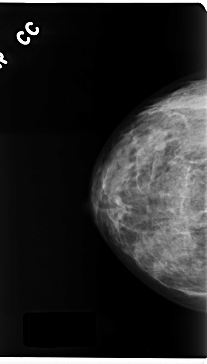

C_0167_1.RIGHT_CC

RIGHT_CC LINES 4728 PIXELS_PER_LINE 2680 BITS_PER_PIXEL 12 RESOLUTION 50 NON_OVERLAY